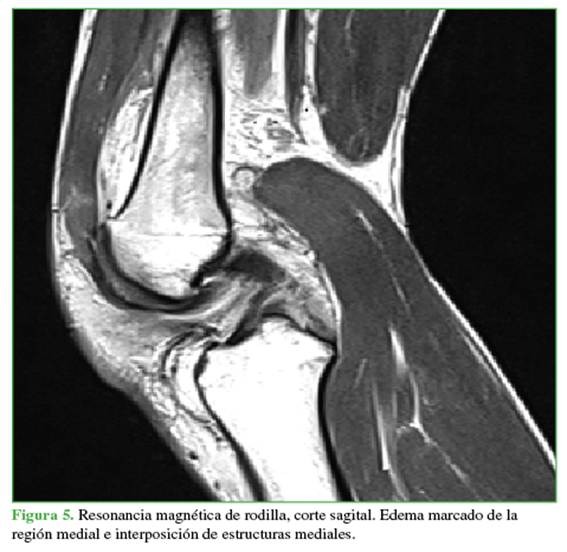

Las radiografías mostraban un aumento del espacio medial debido a la inestabilidad medial. Se ampliaron los estudios con una resonancia magnética (Figuras 4 y 5) para evaluar posibles tejidos o estructuras interpuestos y con una angiotomografía (Figura 6) para descartar una lesión vascular por el tiempo de evolución. Se observó un gran edema en los tejidos mediales, inclusive la cápsula y los tejidos mediales en la zona intercondílea, así como una persistente subluxación de la rodilla. Se descartó un compromiso vascular con integridad del paquete femoropoplíteo.